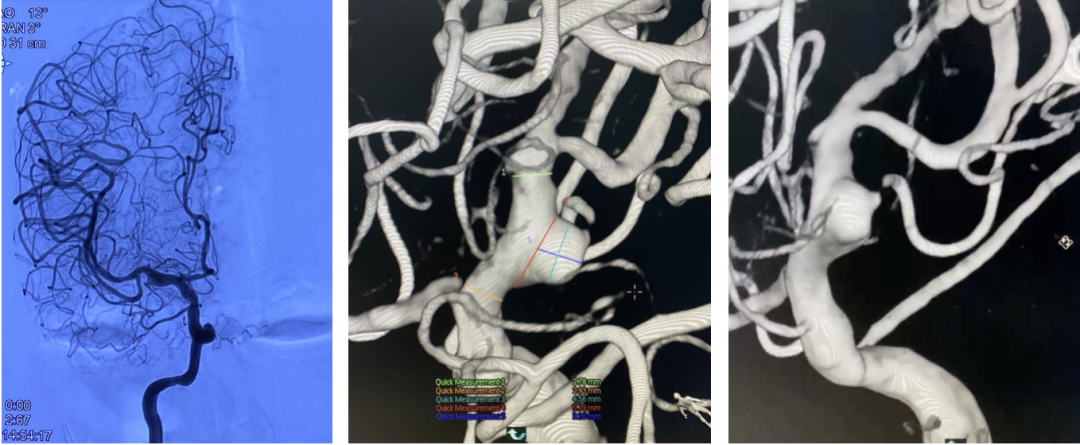

脑血管造影

左侧大脑中分叉处(上干)动脉瘤,夹层可能性大;瘤体4.3mm×5.1mm,瘤颈5.8mm。

远近端载瘤动脉直径分别为2.17mm、2.58mm。